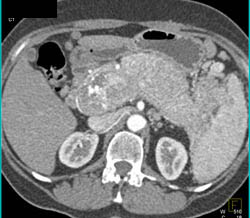

Diagnosis

Intraductal Papillary Mucinous Neoplasm (IPMN)